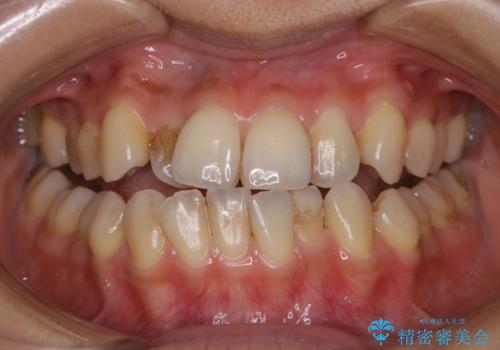

- オフィスホワイトニング希望で1日で白くしたいとのことでした。

オフィスホワイトニングのエクセレントコース(¥29700)を行いました。